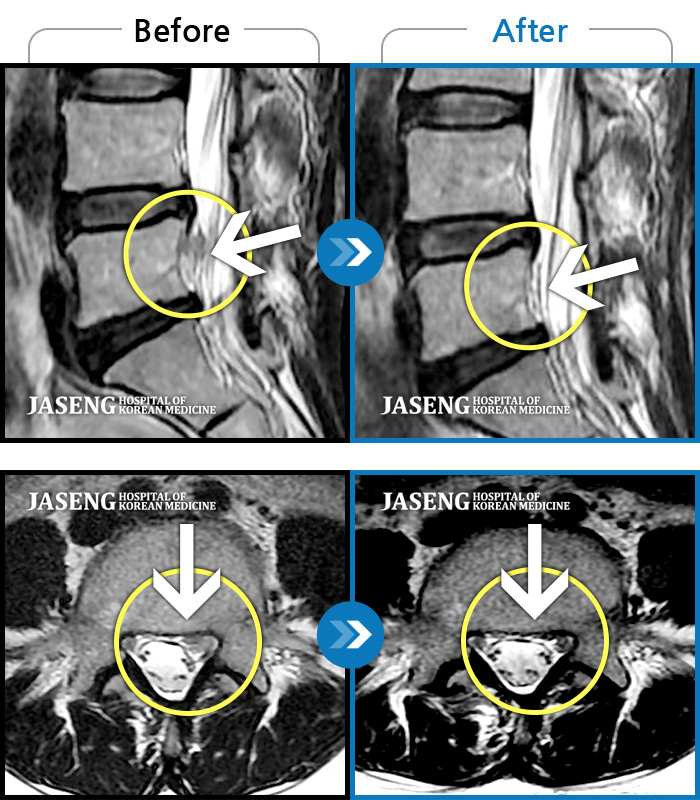

푸쉬업을 여러 번 반복한 뒤 극심한 하요부 통증 및 우측 하지부 저림

2024.03.21 ~ 2024.09.23